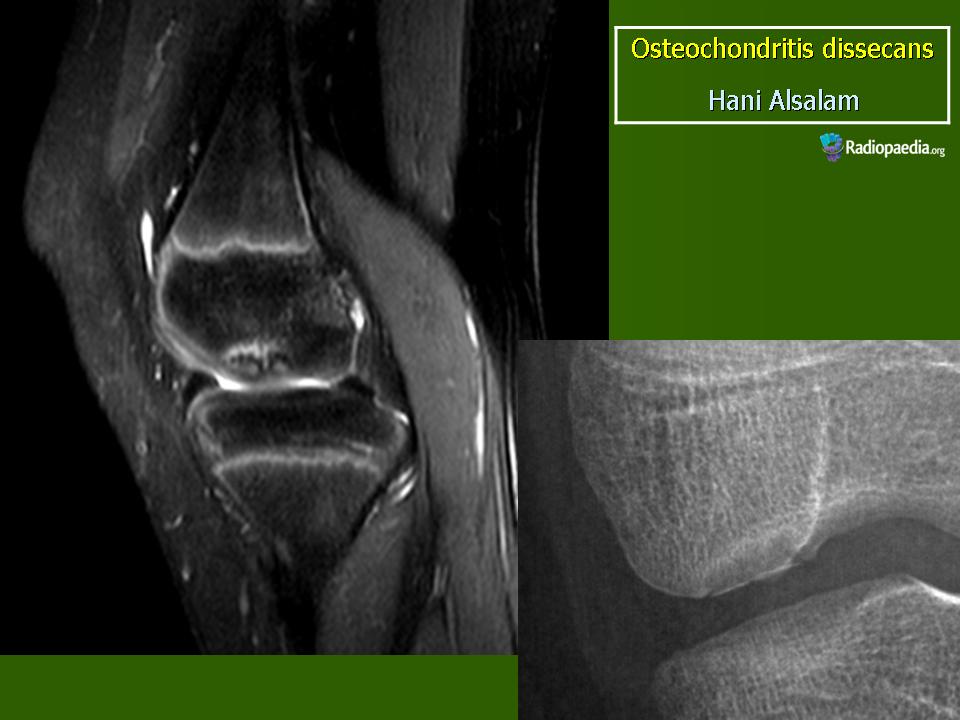

Рентгенологически в I стадии в субхондральной зоне выпуклой суставной поверхности мыщелка бедра выявляется ограниченный участок уплотнения кости. Обычно он двояковыпуклый, достигает размеров 1,0×1,5 см и ограничен узким ободком просветления. Затем (во II стадии) происходит отграничение уплотненного костно-хрящевого фрагмента от материнского ложа: расширяется зона просветления вокруг него, фрагмент начинает выступать в полость сустава (рис. 10). В III стадии определяется ниша в области суставной поверхности мыщелка бедренной кости, а внутрисуставное тело обнаруживается в любой части коленного сустава (обычно, в одном из заворотов, а при блокаде сустава - между суставными поверхностями).

Аналогичные изменения могут наблюдаться и при частичных остеохондропатиях суставных поверхностей головки бедренной, плечевой и лучевой кости, головчатого возвышения плеча, локтевого отростка, блока таранной кости и некоторых других костей.

МРТ.  Рассекающий остеохондрит